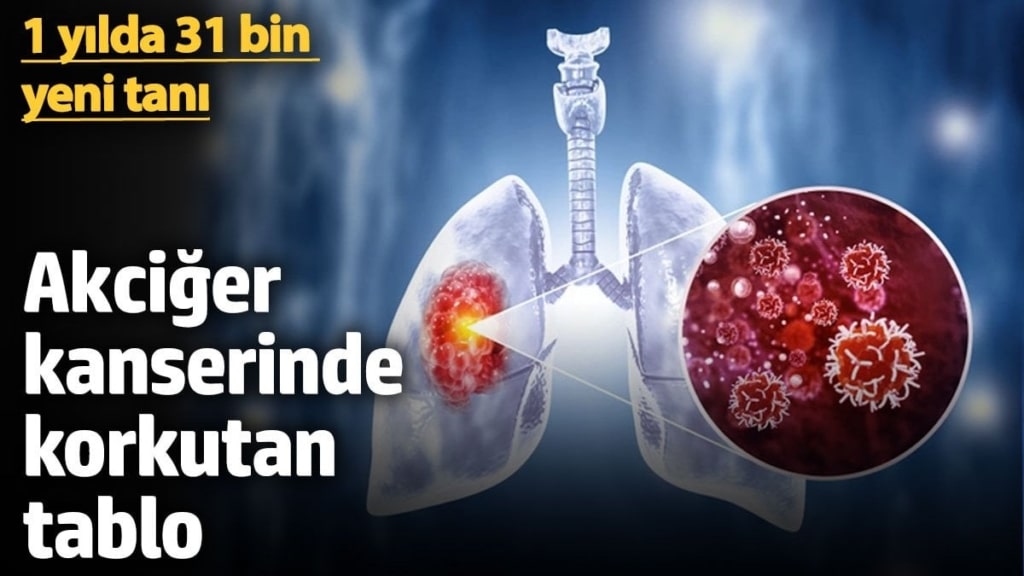

Kansere Yeni Tanı Alanların Sayısı Korkutuyor

Sağlık Bakanlığı, geçtiğimiz yıl içinde önemli bir gündemi ortaya koydu. ‘Akciğer Kanseri Farkındalık Ayı’ vesilesiyle değerlendirmelerde bulunan bir uzman, son bir yıl içinde yaklaşık 30 bin kişinin yeni akciğer kanseri tanısı aldığını duyurdu.

Ölümler Düşünüldüğünde Durum Korkutucu

Akciğer kanserinin, hem dünya genelinde hem de Türkiye’de kanser kaynaklı ölümlerde ilk sırada yer aldığı belirtildi. Uzman, “Ölümlere baktığımızda akciğer kanserine bağlı 25 bine yakın ölüm bildirilmiş” şeklinde ifade etti.

Uzman, akciğer kanseri risk faktörleri arasında sigaranın en önemlisi olduğunu belirtti. Buna ek olarak, “Yalnızca sigarayla sınırlı kalmadığını, tütün ve tütün ürünlerini kapsadığını söylemek daha doğru olacaktır. Sigara dışında nargile ve özellikle elektronik sigaraların da bu maruziyetin büyük bir kısmını oluşturduğunu” kaydetti.

Çevresel Risklere Dikkat

Uzman, asbestin yanı sıra hava kirliliği ve radon gazının da önemli çevresel faktörler arasında yer aldığını ifade etti. Özellikle deprem sonrası ortaya çıkan asbest tozlarının ilerleyen yıllarda kanserojen etkiler yaratabileceğini vurguladı.

Erken Teşhis Hayat Kurtarıyor

Uzman, erken teşhisin son derece önemli olduğuna dikkat çekerek, “Erken teşhis konulduğunda önlenebilir ve tedavi edilebilir bir hastalık, yaklaşık yüzde 70 oranında sağ kalım mevcut. Çok erken tanı aşamasında yakalandığında ise bu oran yüzde 100’e kadar çıkabiliyor” ifadelerini kullandı.